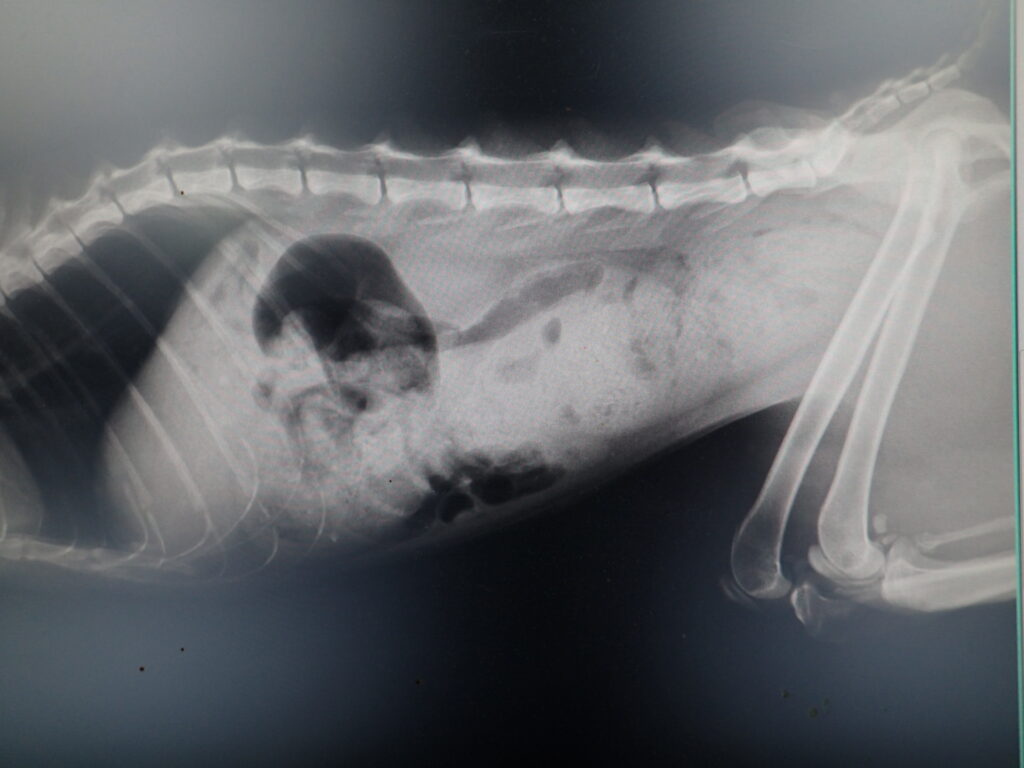

5gを7日間投与

便が軟らかくなり、量も少なくなった。

途中で便が少し押し出されてでてきた。